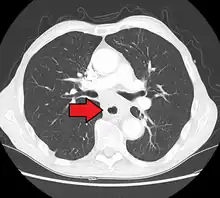

Although an occlusive tumor may be suspected on a barium swallow or barium meal, the diagnosis is best made with an examination using an endoscope. This involves the passing of a flexible tube with a light and camera down the esophagus and examining the wall, and is called an esophagogastroduodenoscopy. Biopsies taken of suspicious lesions are then examined histologically for signs of malignancy.

Additional testing is needed to assess how much the cancer has spread (see § Staging, below). Computed tomography (CT) of the chest, abdomen and pelvis can evaluate whether the cancer has spread to adjacent tissues or distant organs (especially liver and lymph nodes). The sensitivity of a CT scan is limited by its ability to detect masses (e.g. enlarged lymph nodes or involved organs) generally larger than 1 cm.[43][44] Positron emission tomography is also used to estimate the extent of the disease and is regarded as more precise than CT alone.[45] PET/MR as a novel modality has shown promising results in preoperative staging with fair feasibility and good correlation in comparison to PET/CT. It can enhance tissue differentiation with lowering the radiation dose to the patient.[46] Esophageal endoscopic ultrasound can provide staging information regarding the level of tumor invasion, and possible spread to regional lymph nodes.

Contrast CT scan showing an esophageal tumor (axial view)

Contrast CT scan showing an esophageal tumor (coronal view)